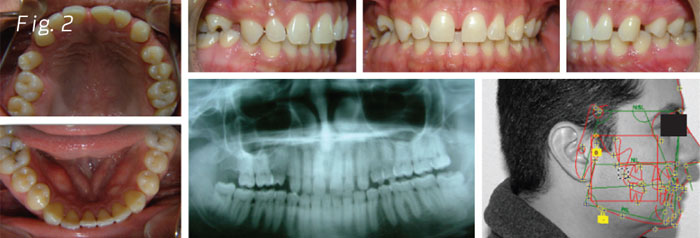

A 34-year-old patient (Fig. 1) wanted to close the spaces between the front teeth and put an implant on the first upper bicuspid (Fig. 2). He didn't want the braces to show so he came to the office for lingual braces.

The patient presented a challenging combination of circumstances, dental spaces, absence of the first upper bicuspid and overbite (Fig. 2).